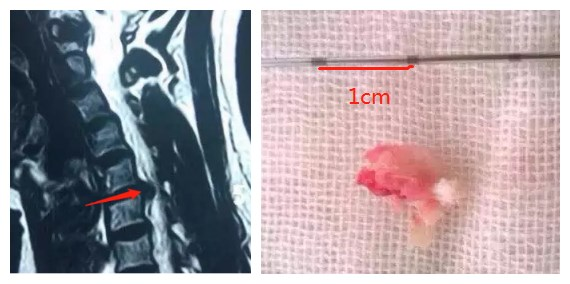

腰椎經(jīng)皮椎間孔鏡手術(shù):主要適用于中青年椎間盤突出且腰椎穩(wěn)定性良好的患者。在局麻或硬膜外麻醉下進(jìn)行,手術(shù)時(shí)間1-2小時(shí),出血10-20ml,手術(shù)切口約1cm,無需植入內(nèi)植物,術(shù)后1天下地活動(dòng),術(shù)后1-3天可出院。

例:23歲男性患者,診斷為“L5/S1椎間盤突出癥”,行椎間孔鏡手術(shù)治療。